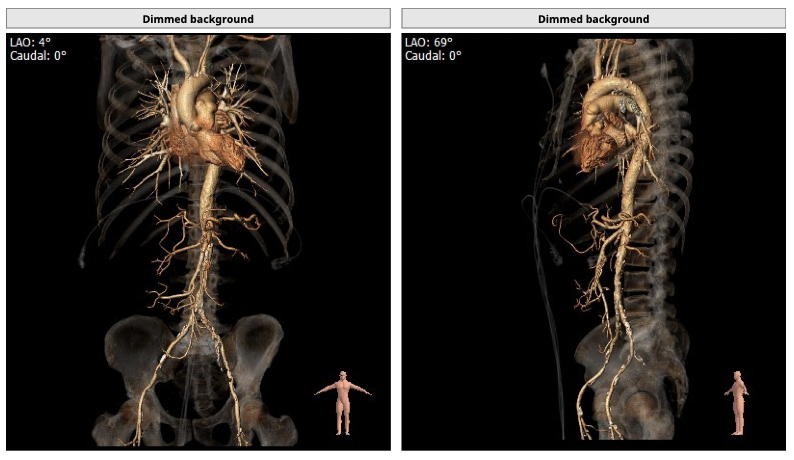

CT检查

①患者因规律透析导致钙磷代谢紊乱,外周血管斑块钙化严重,最狭窄处仅2.8mm,通路建立难度极大(左右颈动脉均不符合入路条件);

②主动脉根部钙化较轻,瓣叶肥厚,各交界缘不同程度粘连,瓣膜释放后具有瓣周漏风险;

③左冠高度不高,且瓣叶冗长,达冠脉开口层面,且冠脉存在狭窄,存在冠脉阻塞的风险;

确保冠脉安全,拟采取PCI+TAVR一站式手术策略,因患者右侧股动脉钙化严重、入路狭窄,拟采取无鞘法从右股动脉穿刺入路,选用20mm球囊预扩、L23号VenusA-Valve瓣膜、采用VenusA-Plus输送系统确保瓣膜的精确释放,瓣膜释放后结合造影和超声情况,决定是否后扩。